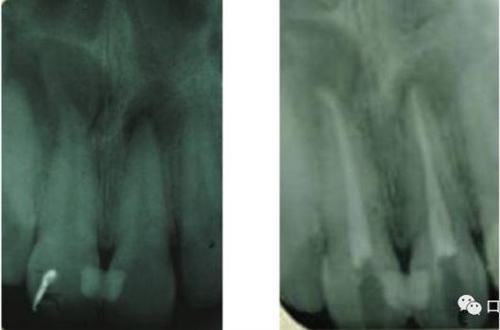

41 治療前X光片

46治療前X光片

治療前和2個月后效果對比